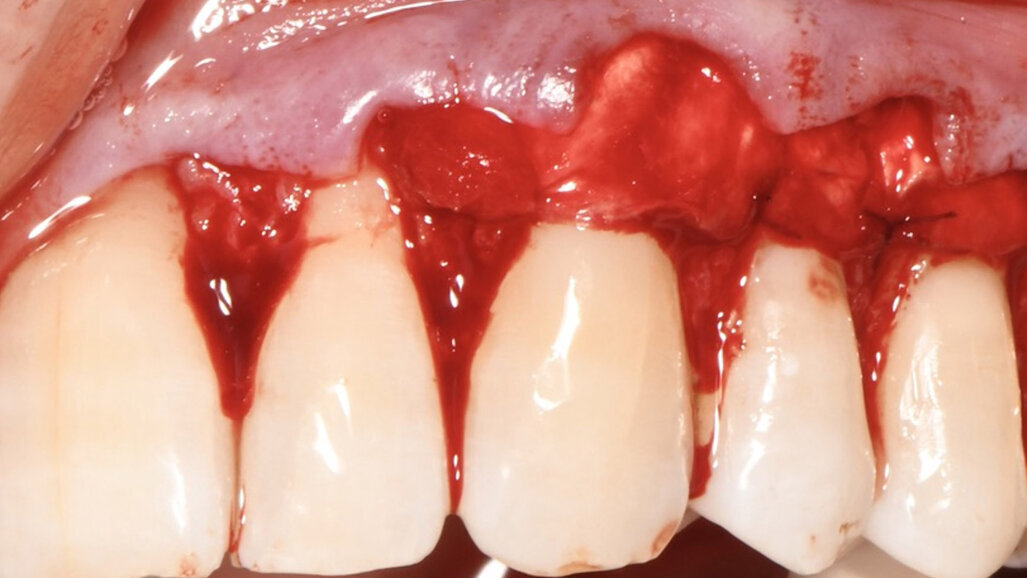

Dopo avere eseguito le incisioni primarie si provvedeva a elevare e mobilitare il lembo con tecnica mista: a spessore parziale in corrispondenza delle papille fino all’altezza del margine apicale delle recessioni, a spessore totale fino al raggiungimento della linea muco-gengivale e infine a spessore parziale apicalmente alla linea muco gengivale per la mobilizzazione in direzione apicale del lembo (Fig. 4). Il sito ricevente è stato trattato mediante levigatura radicolare meccanica della quota di radice esposta in cavo orale dalla recessione e disepitelizzazione delle papille anatomiche. Successivamente la matrice tridimensionale collagenica veniva sagomata in modo da coprire le radici esposte dal 23 al 25 e stabilizzata in sede con suture alla base delle papille anatomiche (Fig. 5). La matrice collagenica, una volta posizionata asciutta nel sito ricevente in modo da facilitarne la sutura, aderiva naturalmente ai tessuti. La matrice veniva suturata senza tensione con punti staccati, alla base delle papille anatomiche, con un filo Polyglactine 6-0 ago 3/8 Reverse - cut Surgicryl (SMI AG Steinberg 8 - 4780 ST.VITH) (Fig. 6).

Fig. 4 - Dettaglio del lembo a busta ottenuto mediante scollamento dai piani sottostanti con tecnica a spessore misto (parziale -totale-parziale).